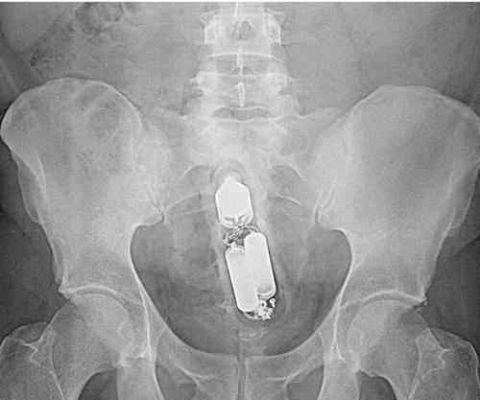

外国人体内的棒棒糖,真会玩